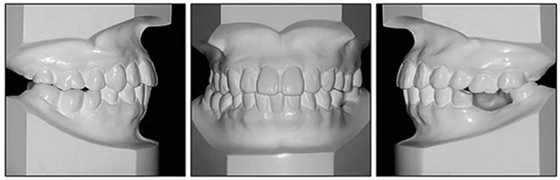

36歲;女性;尋求下頜左后方區(qū)域間隙管理的建議(圖1和圖2),通過治療獲得了良好的牙頜面效果(圖3和圖4)。她被診斷患有骨性I類和代償性牙性II類錯合畸形,并且上頜左側尖牙缺失(圖1和2)。大約七年前,由于不可修復的齲齒,拔除了下頜左側第一和第二磨牙(圖5)。37相鄰的第三磨牙向近中移動并傾斜入間隙,導致無牙頜間隙減小至約14 mm(圖2和圖5)。臨床和影像學評估顯示多發(fā)性齲損和在下頜右側567處有一不良的固定橋修復體(圖1和5)。此外,下頜左中切牙缺失,造成下頜中線向左側偏移約3 mm(圖1和圖2)?;颊咦栽V,她的右上第一前磨牙和左上尖牙在13歲時由其家庭牙醫(yī)拔除,因為它們被阻塞到頰側萌出(圖1)。上頜第二磨牙缺失(未知病因),并且相鄰的第三磨牙已經(jīng)轉移到第二磨牙間隙中。如補充材料所示,美國正畸學差異指數(shù)DI是28分。種植體部位(下頜左側和右側第一磨牙)由于復雜性得到額外4分(補充材料)。

圖1. 治療前面部和口內(nèi)照片